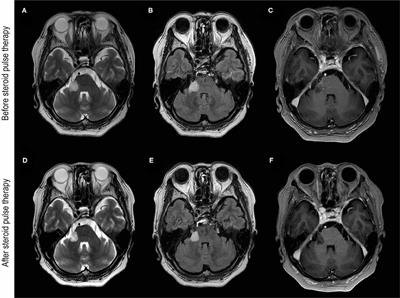

Troubles associés aux anticorps MOG après la vaccination contre le SRAS-CoV-2 : rapport de cas et re...